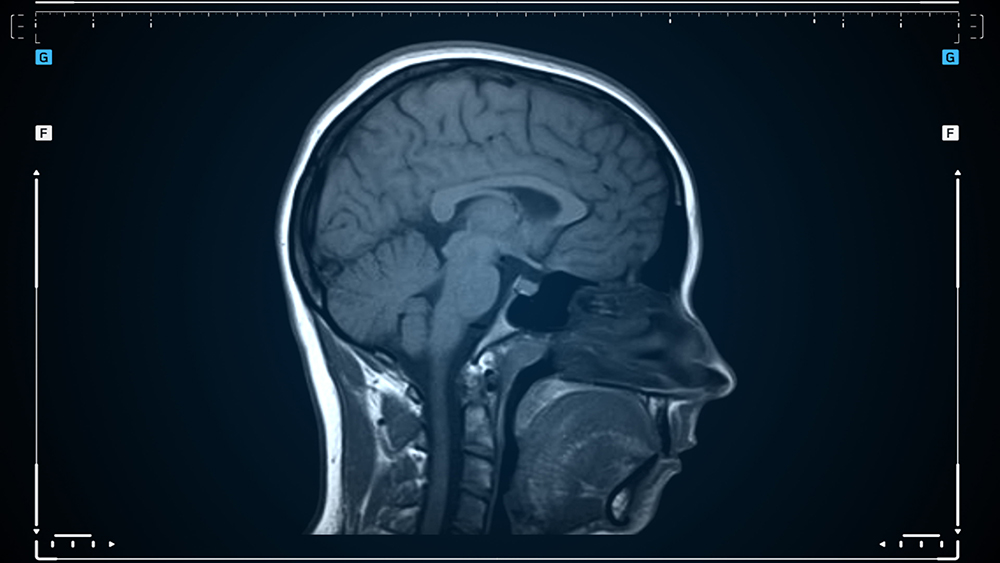

- MRI 및 MRA: 뇌혈관의 구조와 혈류를 확인하기 위한 주요 영상 진단 방법입니다.

- 뇌혈관 조영술: 모야모야병의 확진을 위해 가장 효과적인 검사로, 뇌혈관의 비정상적인 모양을 정확히 확인할 수 있습니다.